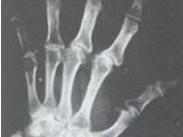

卡斯欽-貝克病(Kaschin-Beck disease)即大骨節(jié)病,是一種地方性軟骨骨關(guān)節(jié)畸形病,是以軟骨壞死為主的變形性骨關(guān)節(jié)病。多發(fā)生于兒童和少年,主要侵犯兒童和青少年的骨骼與關(guān)節(jié)系統(tǒng),導(dǎo)致軟骨內(nèi)成骨障礙、管狀骨變短和繼發(fā)的變形性關(guān)節(jié)病。致管狀長骨發(fā)育障礙,關(guān)節(jié)增粗、疼痛、肌肉松弛、萎縮和運(yùn)動障礙?;颊咭陨聿陌?、短指、關(guān)節(jié)畸形、步態(tài)異常(呈典型跛行、鴨步)等為特征。本病尚有“矮人病”、“算盤子病”、“柳拐子病”等之稱。

- 常見癥狀:軟骨發(fā)育不良與骨骼畸形、肌肉萎縮、指(趾)和小腿出現(xiàn)痙攣及隱痛、步態(tài)異常、體型異常、關(guān)節(jié)疼痛